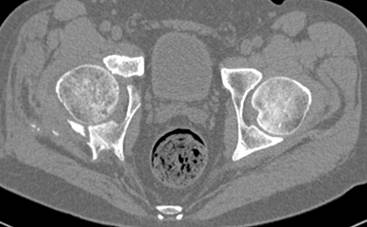

[Ortho] перелом правой половины таза

высылаю дополнительно  сканы.